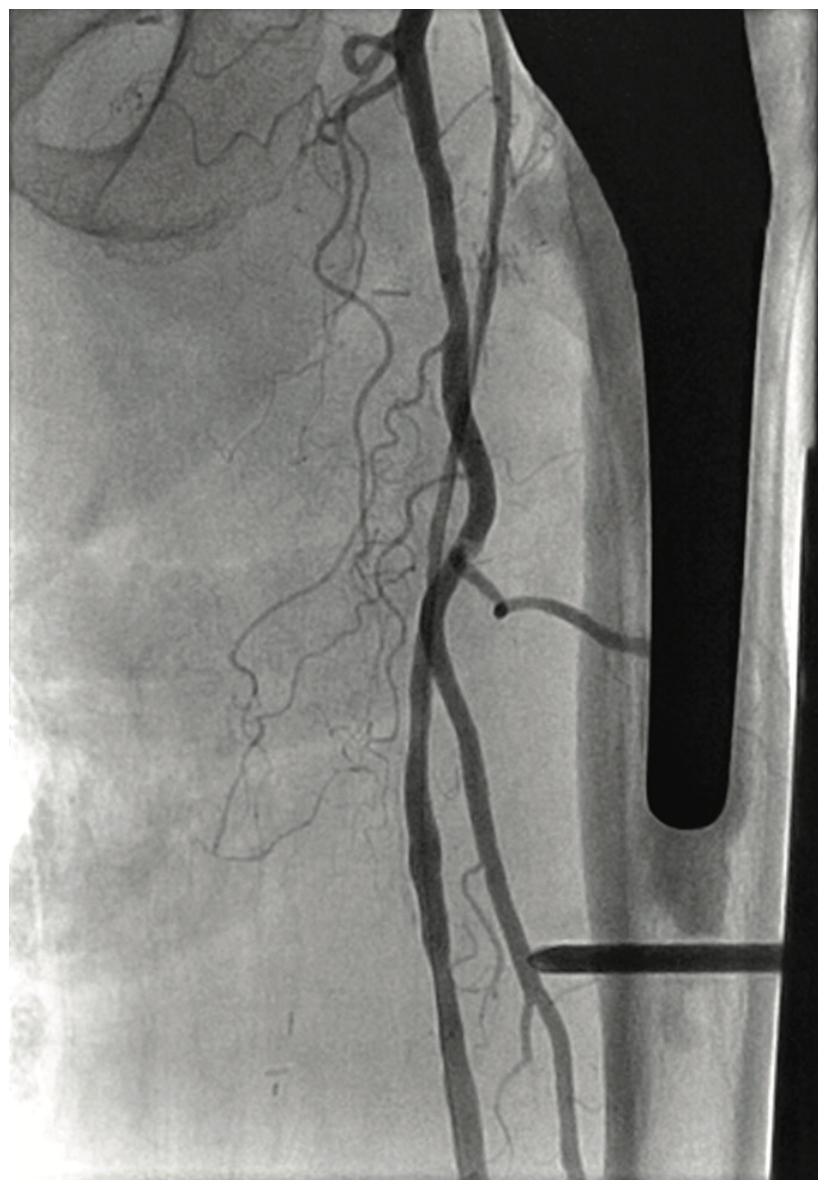

A 73-year-old former smoker presented with severe and progressive claudication of her left leg with resting foot pain. Her symptoms first began 35 years ago and approximately 10 years ago, she had a left iliac artery occlusion that was treated with recanalization and stenting. At the same time, her SFA was treated, but after multiple interventions had failed, she underwent fem-pop bypass grafting. Unfortunately, she suffered a graft infection and had to have the fem-pop graft removed. She was told by her vascular surgeon nothing could be done. She now presented with calf claudication and resting pain. A 6 French Ansel (Cook Medical) also confirmed the left SFA was occluded at the origin, with an extensive network of collaterals from the deep femoral artery (Figure 13). We passed a Frontrunner catheter (Cordis) through the CrossLock with the CrossLock inflated for super support (Figure 15). We also passed the CrossLock over the Frontrunner with the CrossLock balloon deflated. The balloon support catheter and Frontrunner were removed. Focused balloon dilation and multiple drug-eluting balloon dilations (Lutonix, Bard Peripheral Vascular) were performed. Excellent 3-vessel runoff was visualized on angiography (Figure 16).